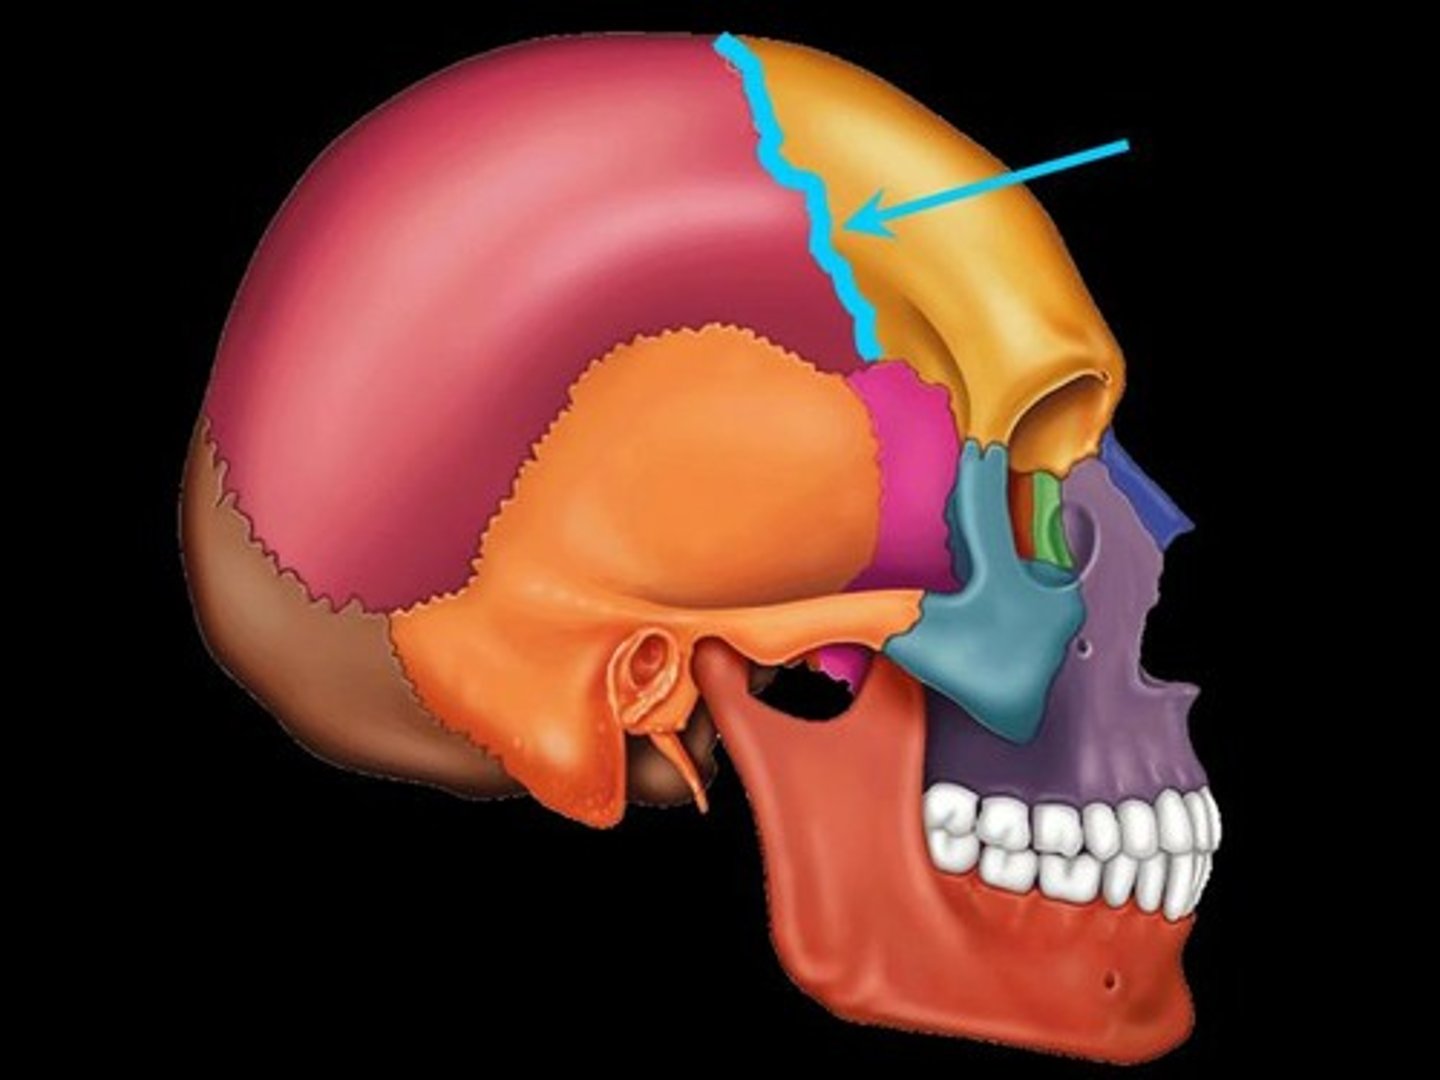

Types of fibrous joints

-suture

-gomphoses

-syndesmoses

Fibrous joints

consists of inflexible layers of dense connective tissue, holds the bones tightly together

-solid joints

Sutures

occurs only in the skull where adjacent bones are linked by a thin layer of connective tissue

Sutural ligament

thin layer of dense connective tissue that joins flat bones of the skull together